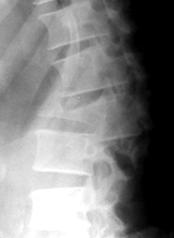

Признаками сгибательно-дистракционного повреждения является увеличение расстояния между соседними остистыми отростками на прямой и боковой рентгенограмме (рис. 3А) и локальный кифоз (рис. 3Б).

|

| А |

Б |

| Рис. 3. Рентгенологические признаки сгибательно-дистракционного повреждения |